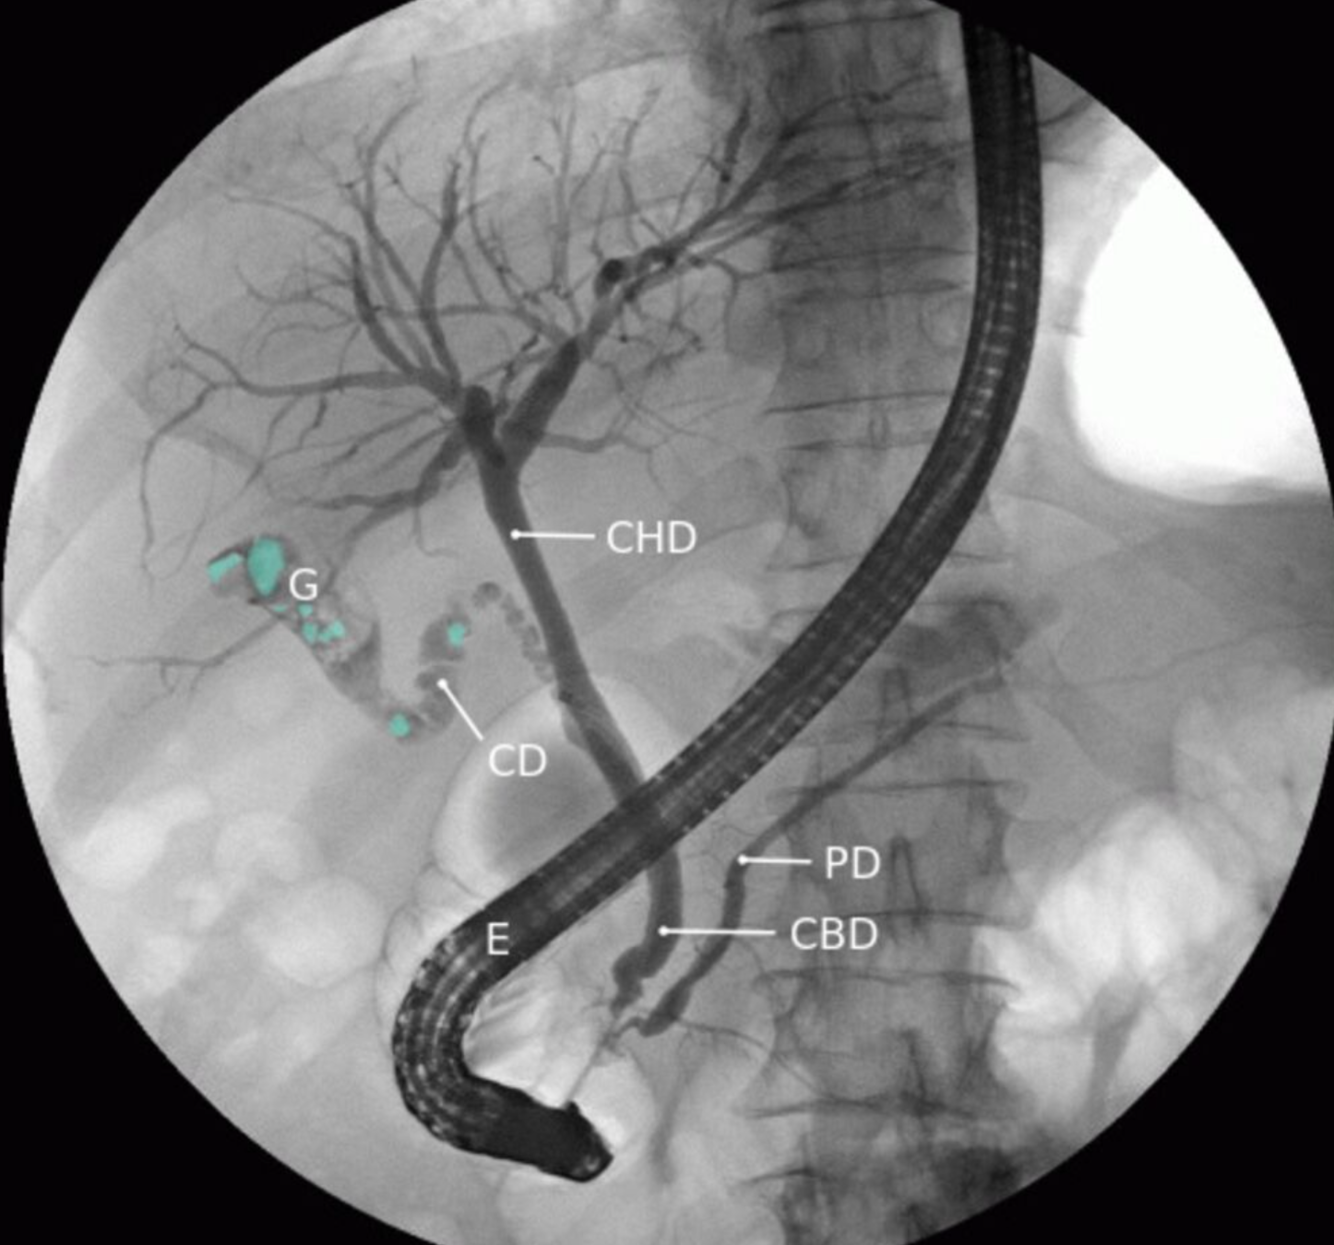

Cholangiopancréatographie rétrograde endoscopique (CPRE)

La pointe de l’endoscope (E) est située dans le duodénum au niveau de l’ampoule de Vater. L’amélioration du contraste permet de visualiser les voies biliaires hépatiques, les canaux hépatiques gauche et droit, le canal cystique (CD), la vésicule biliaire (G), le canal cholédoque (CBD) et le canal pancréatique (PD). Plusieurs défauts de remplissage (exemples indiqués par une superposition verte) peuvent être observés dans la vésicule biliaire et le canal cystique.

Cette constatation est le diagnostic de lithiase biliaire.